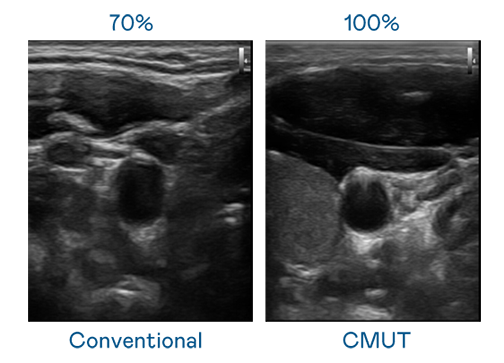

CMUT 技術是一種用電容式微機電元件來產生超音波訊號的技術。與傳統 PZT 壓電式技術相比,CMUT 頻寬增加 30%,更寬頻的超音波訊號讓影像解析度大幅提升,是實現高影像品質醫療超音波掃描、促進精準醫療發展的關鍵技術。

大頻寬帶來超清晰影像

超音波影像的解析度高低,首先取決於探頭能發出的訊號頻寬。爱游戏网页版官方入口 CMUT 可提供高清晰的超音波訊號,提供高頻寬、高靈敏度、影像紋理細節更高的超音波影像,協助醫護人員縮短影像判讀時間及利用精準的醫療影像進行診斷。